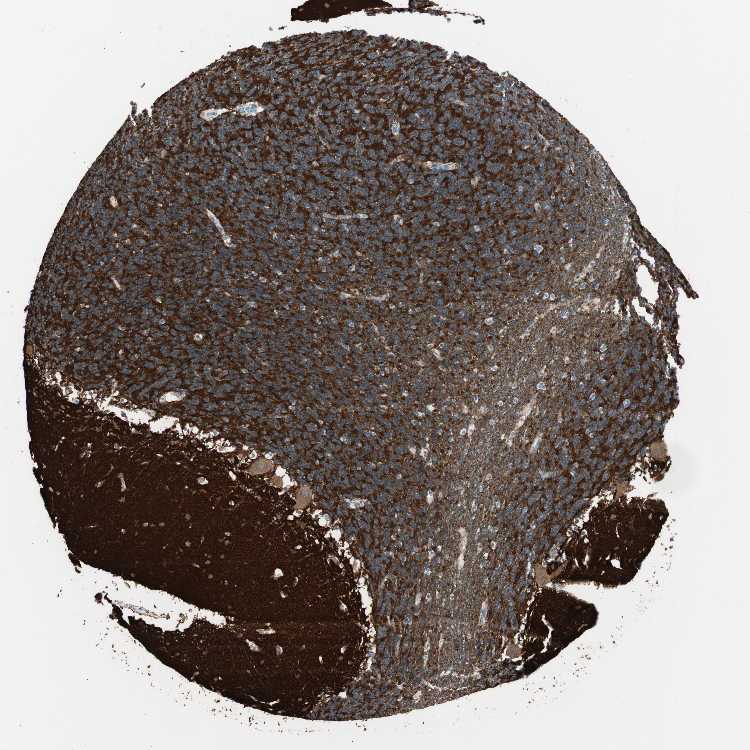

BRAIN CEREBELLUM Show tissue menu

CEREBELLUM - Antibody stainingi

Antibody staining in the annotated cell types in the current human tissue is reported as not detected, low, medium, or high, based on conventional immunohistochemistry profiling in selected tissues. This score is based on the combination of the staining intensity and fraction of stained cells.

Each image is clickable and will lead to virtual microscopy that enables deeper exploration of all samples and also displays staining intensity scores, fraction scores and subcellular localization as well as patient and tissue information for each sample.

Antibody HPA040878Antibody CAB008387

Molecular layer - neuropil High-

Processes in granular layer High-

Processes in white matter High-